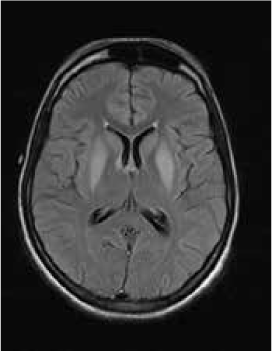

Magnetic resonance imaging (MRI) of the brain showed symmetrically increased T2-weighted and fluid-attenuated inversion recovery signal in the central pons (Figure 1) and in the striatum of the basal ganglia (Figure 2), with no contrast enhancement seen on corresponding T1-weighted postgadolinium images (Figures 3 and 4). Spinal MRI (Figure 5) demonstrated high signal on T2-weighted images from the area postrema in the medulla extending caudally to the T9 thoracic segment, with marked cord swelling and mild enhancement on T1-weighted postcontrast studies (Figure 6), in keeping with a longitudinally extensive inflammatory myelitis.

Postcontrast magnetic resonance image of brain show nonenhancing changes in basal ganglia

The clinical and radiologic features supported the diagnosis of NMO. However, the symmetrical pontine and basal ganglia high signal without contrast enhancement were considered to be strongly suggestive of concomitant ODS (pontine and extrapontine myelinolysis).

Neuromyelitis optica may lead to hyponatremia via at least two mechanisms. Area postrema involvement frequently causes intractable vomiting, and this may result in a low serum sodium level. Moreover, the syndrome of inappropriate antidiuretic hormone may develop in patients with NMO and hypothalamic lesions. In the present patient, the lowest recorded sodium level was 132 mmol/L. However, MRI demonstrated features of both central pontine and extrapontine myelinolysis, which, when occurring together, are considered virtually pathognomonic of ODS.4 Typical features include the symmetrical nature of the changes, the involvement of areas typically affected in ODS (pons, basal ganglia), and the sparing of peripheral pontine fibers. However, it remains a possibility that these radiologic changes were due to NMO primarily rather than osmotic demyelination. In a recent review, Kim et al.5 expanded on the range of MRI abnormalities consistent with NMO and NMO spectrum disorders. Gray matter demyelination of the thalamus and bilateral involvement of the corticospinal tracts have been described, although published examples are not as strikingly symmetrical as in this case and do not show the combination of central pontine demyelination with symmetrical striatal involvement.5 To our knowledge, these typical ODS changes in the context of NMO have been described in only one other case, in the Japanese literature.6